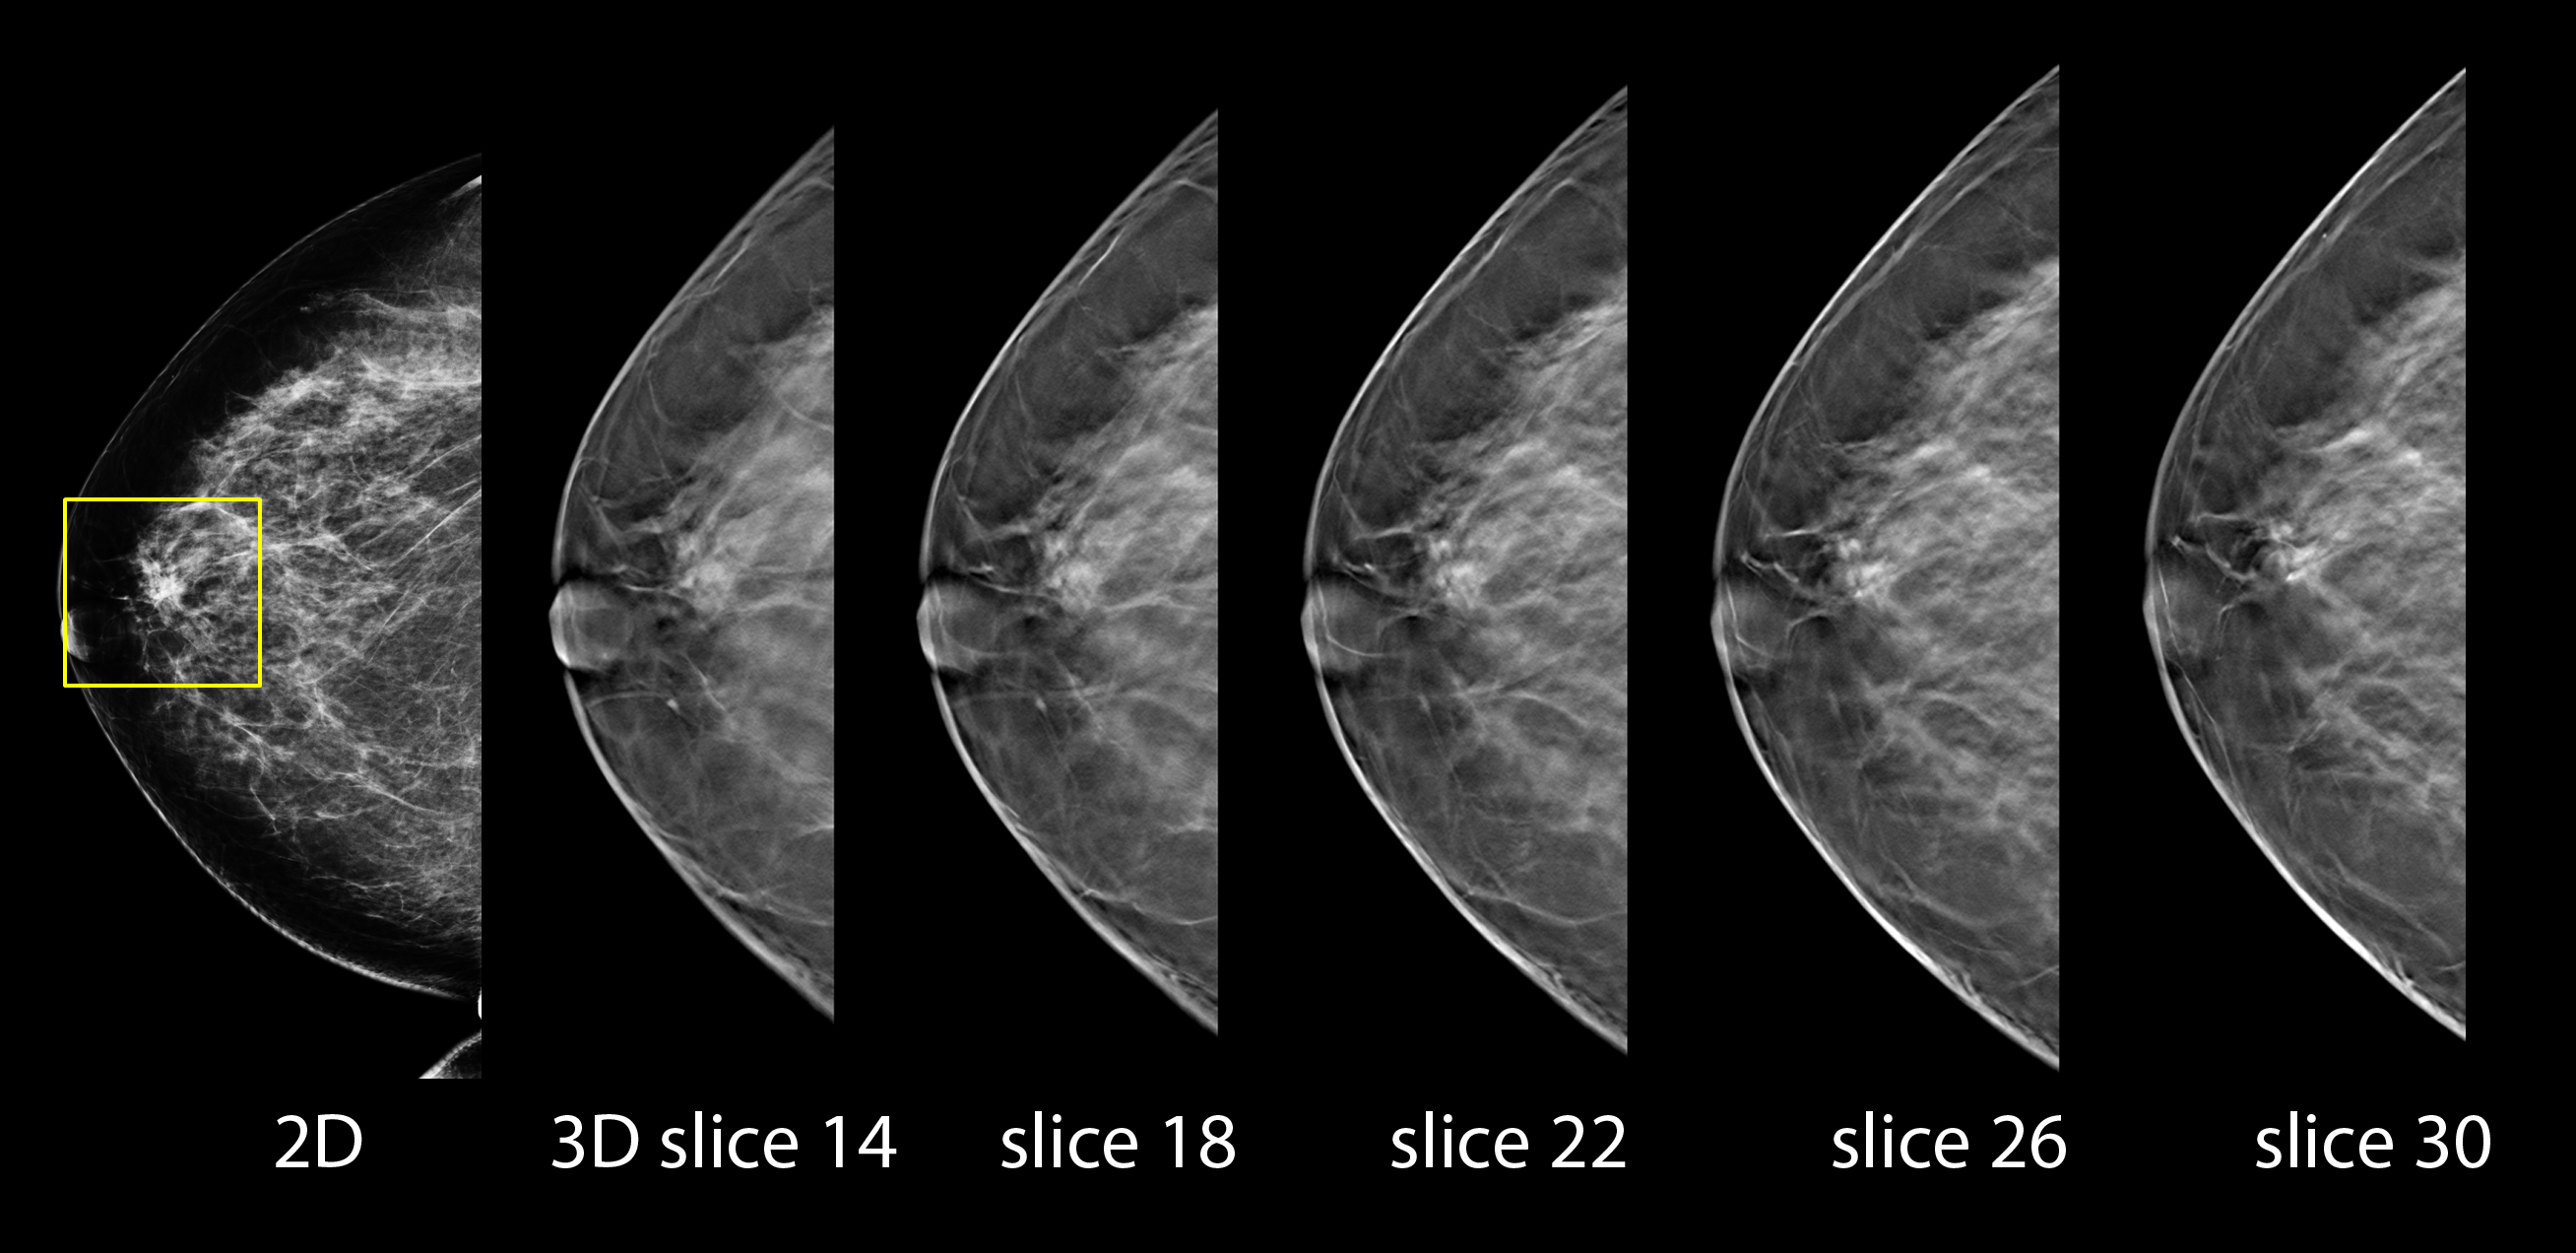

Hologic  - Selenia Dimensions 3D - Tomosynteza piersi

Selenia Dimensions 3D dostarcza silne narzędzia w oparciu o tomosyntezę piersi umożliwiające lepszą wizualizacje zmian.

Najnowsza technologia w obrazowaniu piersi charakteryzuje się lepszym współczynnikiem wykrywania w stosunku do metody konwencjonalnej i jednocześnie redukuje ilość wykrywanych zmian negatywnie pozytywnych.

Zamiast obrazów nakładających się struktur w piersi (charakterystyczna dla tradycyjnych mammografów 2D), lekarz radiolog ma możliwość zidentyfikowania poszczególnych płaszczyzn bez problemów wynikających z nakładania się ich na siebie. Podczas skanowania z tomosyntezą jest wykonywana seria zdjęć piersi pod różnymi kontami przy zmniejszonej  dawce promieniowania. Obrazy te są następnie użyte do wytworzenia serii cienkich (1- milimetrowych)  obrazów warstw, które mogą być przeglądane jako trójwymiarowy  zrekonstruowany obraz piersi. To nowe, rewolucyjne spojrzenie na strukturę piersi zwiększa możliwości w diagnostyce raka piersi.

Wyjątkowa elastyczność pracy z każdym pacjentem

Selenia Dimensions została zaprojektowana jako uniwersalna platforma do każdego typu obrazowania piersi. Łatwy sposób wyboru opcji pracy przez operatora umożliwia przełączanie się pomiędzy trzema trybami pracy: konwencjonalne obrazowanie 2D, obrazowanie z tomosyntezą 3D oraz tryb COMBO – umożliwiający wykonanie obrazowania 2D i 3D w trakcie jednego cyklu (pierś uciskana jest jednokrotnie).  Taki elastyczny sposób obrazowania daje radiologom możliwość wyboru typu badania dostosowanego do konkretnego pacjenta.

W momencie gdy badanie jest wykonywane w trybie „combo” po uciśnięciu piersi w tradycyjny sposób lampa wykonuje ruch obrotowy o 15 stopni wykonując serię 15 zdjęć z niska dawką pod różnymi kontami. Te projekcje są następnie użyte do rekonstrukcji poszczególnych warstw. Bezpośrednio po zakończeniu skanowania klatka przeciwrozproszeniowa jest wsuwana w obszar obrazowania i wykonywane jest tradycyjne zdjęcie 2D.

Cała operacja trawa kilka sekund i daje radiologom oba typy obrazów – tradycyjny mammogram  i obrazy z tomosyntezą podczas jednego ucisku piersi. Umożliwia to pełne wzajemne odpowiadanie sobie obu obrazów.